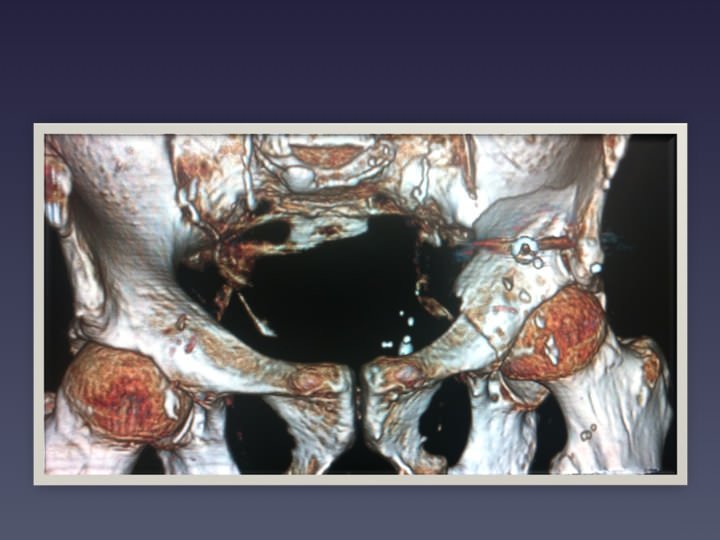

• BASSIN HANCHE

• FRACTURES DU BASSIN

• OSTEOPLASTIE ET OSTEOSYNTHESE SOUS GUIDAGE SCANNER

• OSTEOSYNTHESE

• RSNA 2012 VISSAGE DES FRACTURES COTYLOÏDIENNES

• OSTEOSYNTHESE SOUS SCANNER